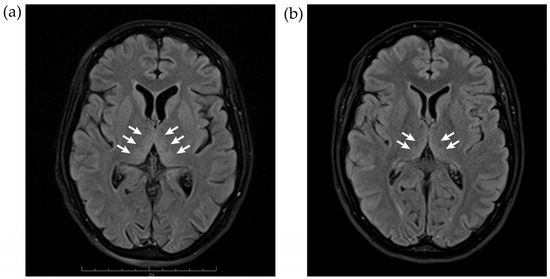

3.5. Imaging